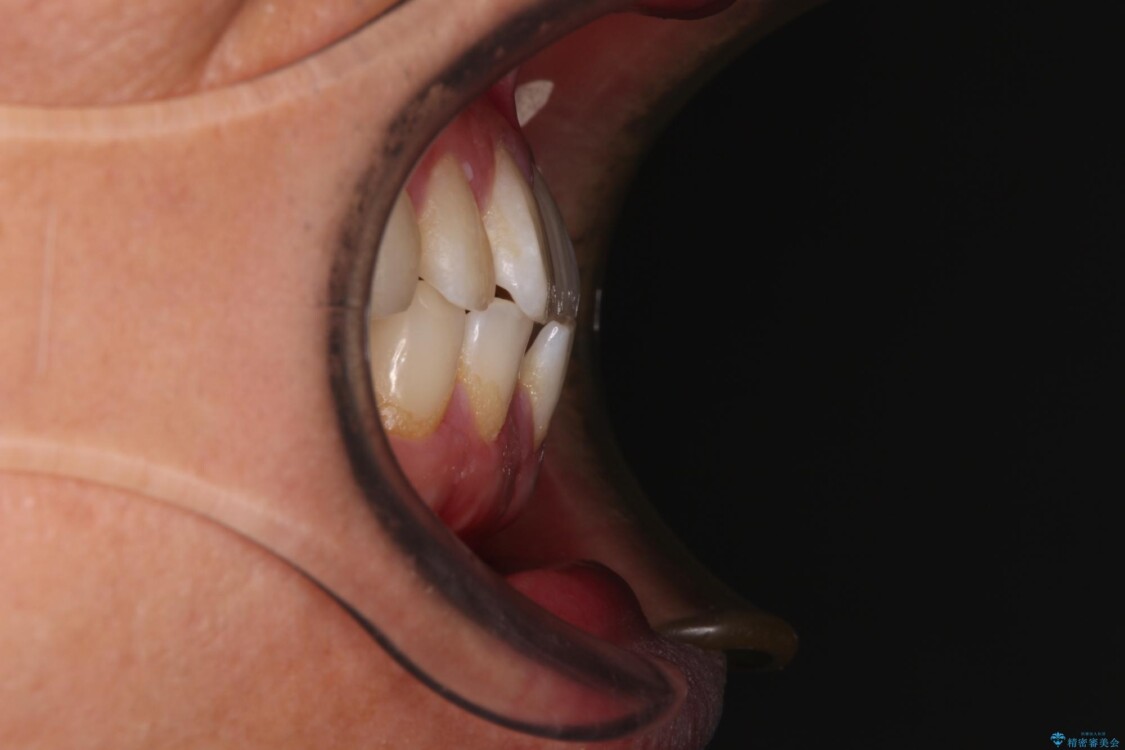

主訴:前歯のデコボコと奥歯のかみ合わせを治したい 今回ご紹介するのは、「前歯のガタガタ(叢生)」と「奥歯のかみ合わせ(シザーズバイト)」にお悩みでご来院された患者様の症例です。 患者様は、 ・歯並びをできるだけ早く改善したい ・費用を抑えた矯正治療 というご要望をお持ちでした。

・上顎左右の第二大臼歯が頬側へ転移し、シザーズバイト(scissors bite)の状態

・上顎左側第二小臼歯が90度捻転しており、噛み合わせに影響

治療前

• 前歯のガタガタ・奥歯のかみ合わせ(シザーズバイト)を改善|1年半で完了したメタルブラケット矯正 治療前画像